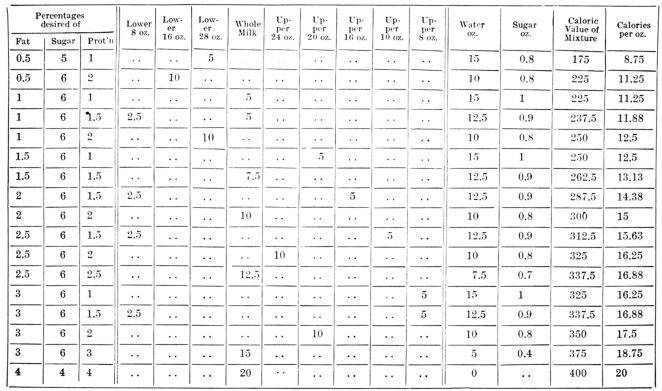

| 171. | Dr. Griffith’s table of fat percentages | 500 |

| 172. | Reverse side of above card | 501 |